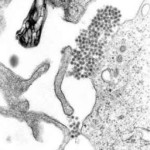

Los investigadores aislaron el anticuerpo humano, HM14c10, que se formó en el cuerpo de un paciente en Singapur que se había recuperado de una infección DENV1. El anticuerpo resultó ser extremadamente de acción rápida y potente dio inmunidad al virus.

El grupo reclutó a alrededor de 100 pacientes con dengue que se recuperaron y se encontraran a más de 200.000 anticuerpos en total. El anticuerpo HM14c10 resultó ser tan poderoso que mata el virus antes de que sea capaz de infectar a las células, según el investigador, el profesor Lok de la Universidad Nacional de Singapur.

Después de aislar el anticuerpo, los investigadores llevaron a cabo experimentos en ratones y descubrieron que las funciones de que se extiende por la superficie del virus, evitando que los cambios en las proteínas de su superficie que deben tener lugar para que el virus pueda infectar a las células.